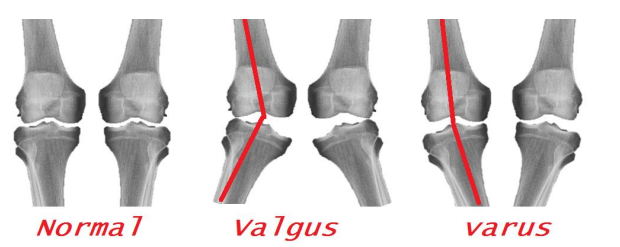

With chronic MCL injuries, calcification at the medial femoralinsertion site may be seen. This is known as a Pellegrini-Stieda lesion (Figure5).

Figure 5: A Pellegrini-Stieda lesion. A sliver of calcification is shown by the arrow.